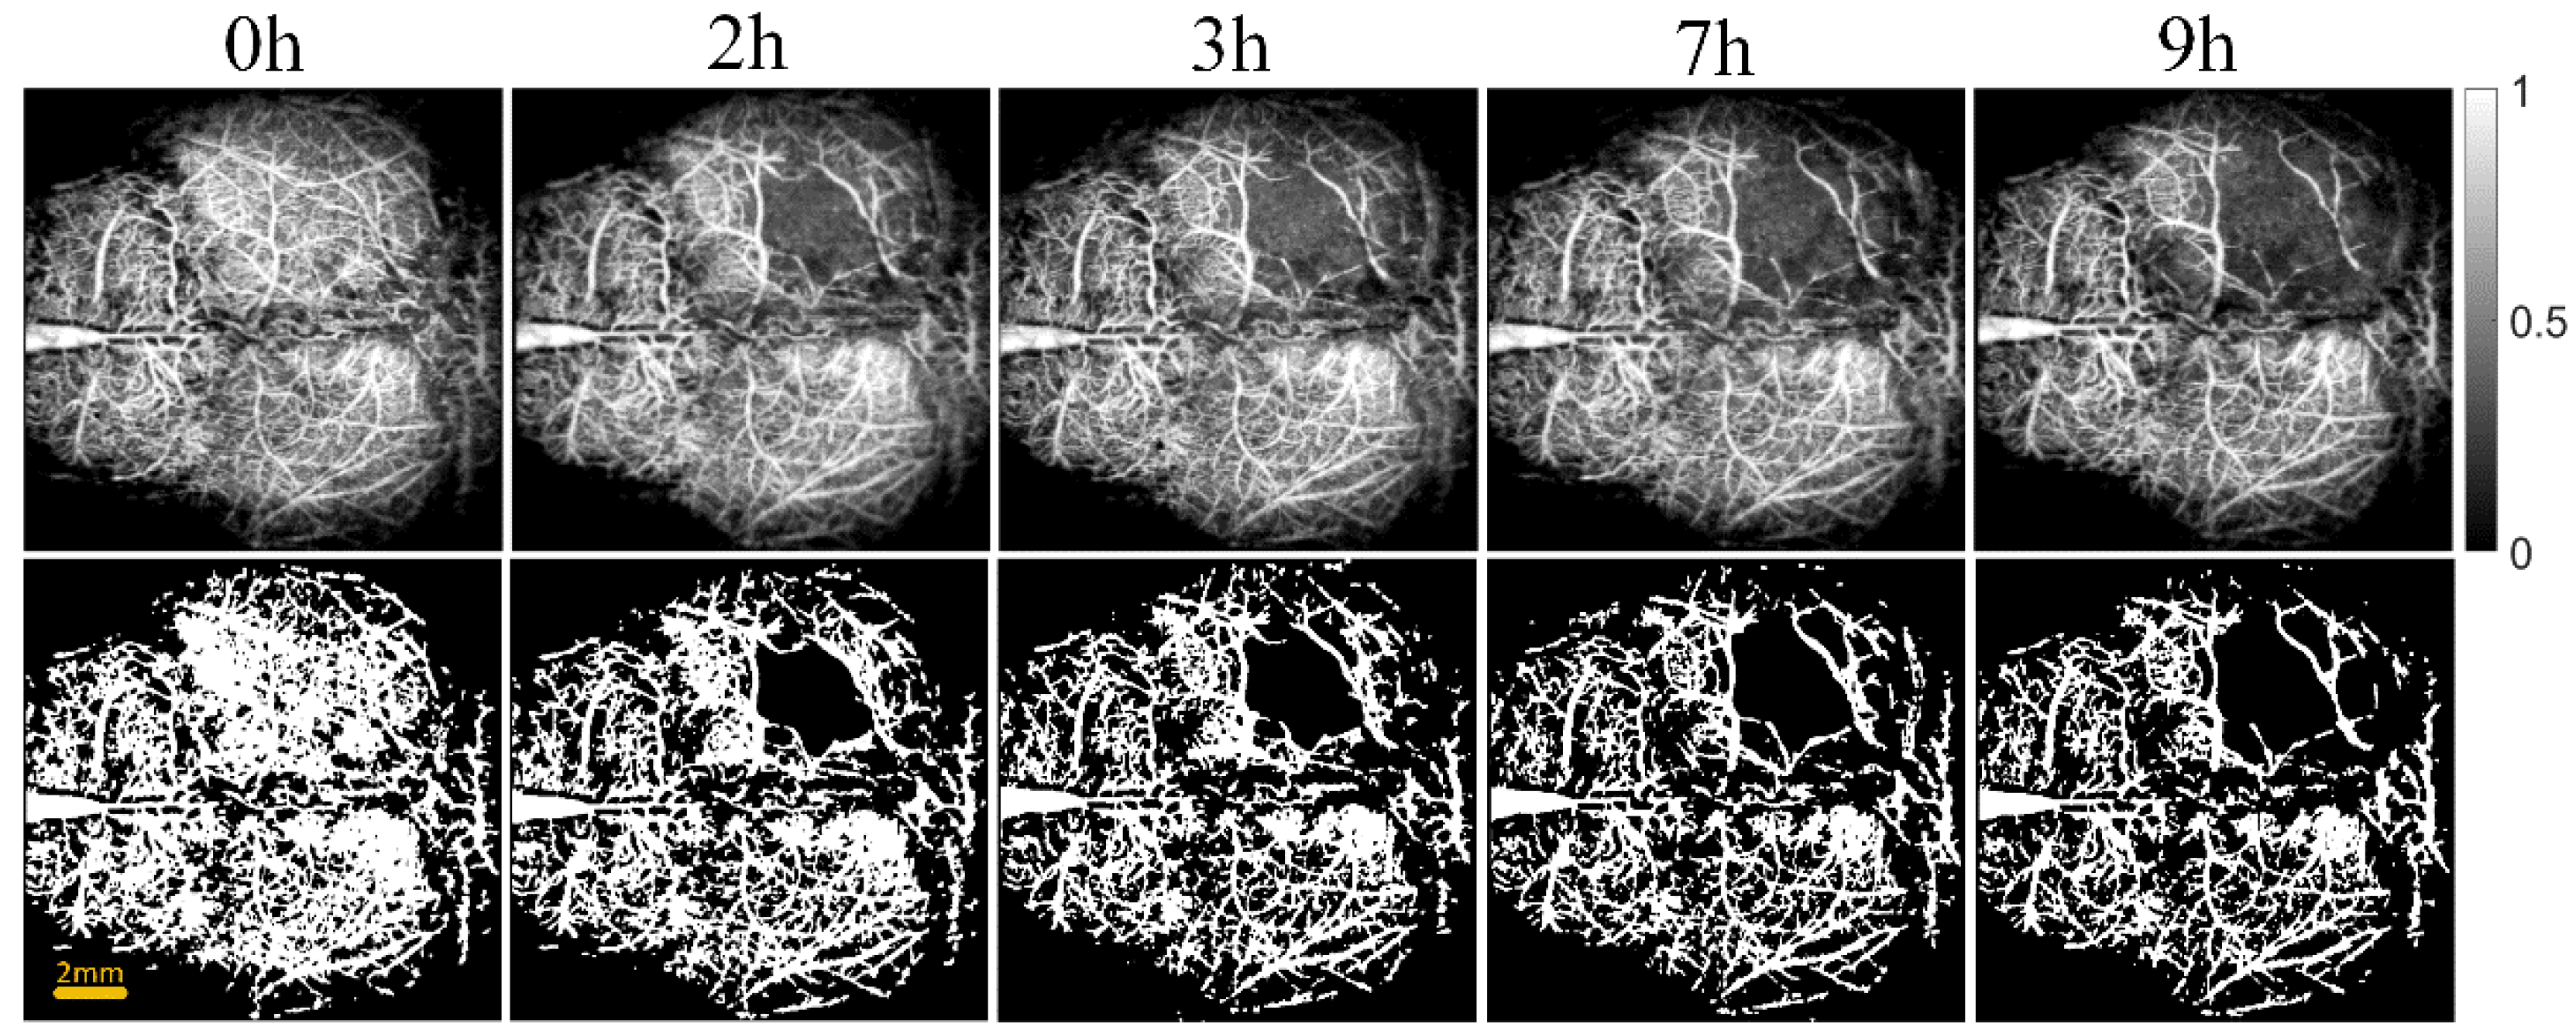

2.2.3. Blood Vessels Segmentation

2.2.4. Quantification of Vascular Parameters

2.2.5. OCT Attenuation Imaging

2.2.6. Quantization of Edema Parameters